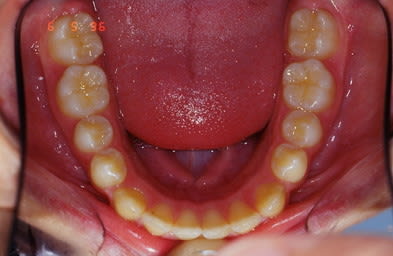

voici le 1er cas

Biproalveolie

QH + Reeducation + Ecran buccal c'est tout

cas 1 suite et fin

Noter la fermeture des diastemes infer. sans aucune mecanique